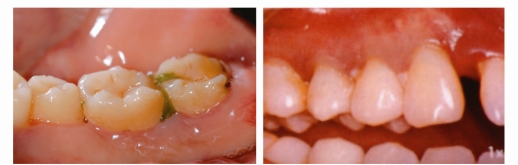

反复的牙龈肿痛溢脓

有些患者牙龈反复“长包”,并且有黄色的脓液流出,这就是牙周炎症导致的“牙周脓肿”。